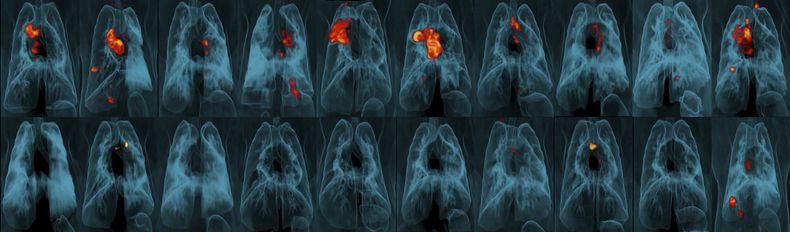

Seis meses después de las vacunaciones, los investigadores colocaron la bacteria de la tuberculosis directamente en los pulmones de los animales y observaron para ver si se infectaban. Los monos que recibieron la inyección subcutánea que se usa actualmente, incluso en una dosis más elevada, sólo estaban ligeramente más protegidos que los animales no vacunados y el rocío tampoco fue muy efectivo.

Sin embargo, en 9 de cada 10 monos, una dosis de vacuna más elevada de lo usual inyectada a una vena funcionó mucho mejor, reportaron los investigadores en la revista Nature. El equipo no halló rastros de infección en seis de los animales y contabilizó niveles muy bajos de bacterias de la tuberculosis en los pulmones de tres.

¿A qué se debe? La hipótesis es que células inmunológicas clave llamadas linfocitos T tienen que llenar los pulmones para matar a las bacterias de tuberculosis y pueden hacerlo con mayor rapidez cuando la vacuna es transportada rápidamente a través del torrente sanguíneo. Las pruebas mostraron linfocitos T más activos que permanecían en los pulmones de monos vacunados de la nueva forma.